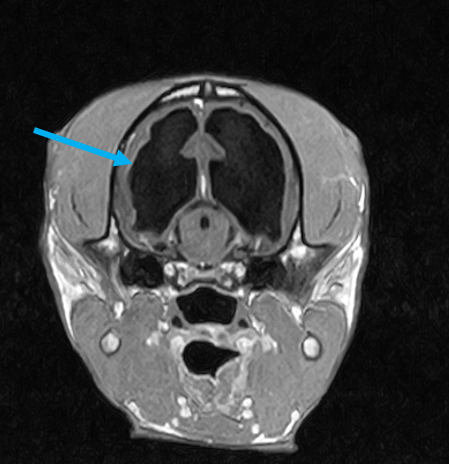

W obrębie mózgowia i trzewioczaszki najczęstszymi wskazaniami do badania MRI są:

• proces nowotworowy

• wodogłowie

• ziarniakowe zapaleniu mózgu i opon mózgowych

• diagnostyka zmian udarowych

• wstępna diagnostyka tętniaków i malformacji naczyniowych

• wstępna diagnoza gruczołu przysadki

• ocena patologii ucha zewnętrznego, środkowego oraz wewnętrznego

• patologie w obrębie oczodołów i struktur przyległych – ocena zmian pourazowych, zapalnych i nowotworowych

• zmiany zaoczodołowe i około zębowe – diagnostyka przewlekłych infekcji